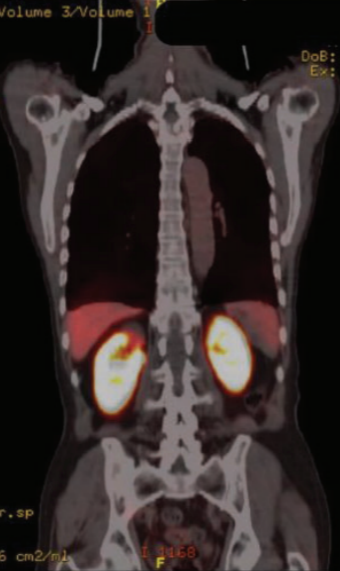

为了确定病灶起源并排除前列腺癌

转移,进行了Ga-68 PET-CT,成像显示PET-CT标记的病灶没有显著的同位素摄取(图2)。因此,第六肋骨、髂骨和股骨上的病变被认为是卡波西肉瘤转移灶。患者拒绝干扰素治疗。一年后,患者出现了持续性贫血

图2 患者确诊为前列腺癌时的Ga-68 PET-CT图像